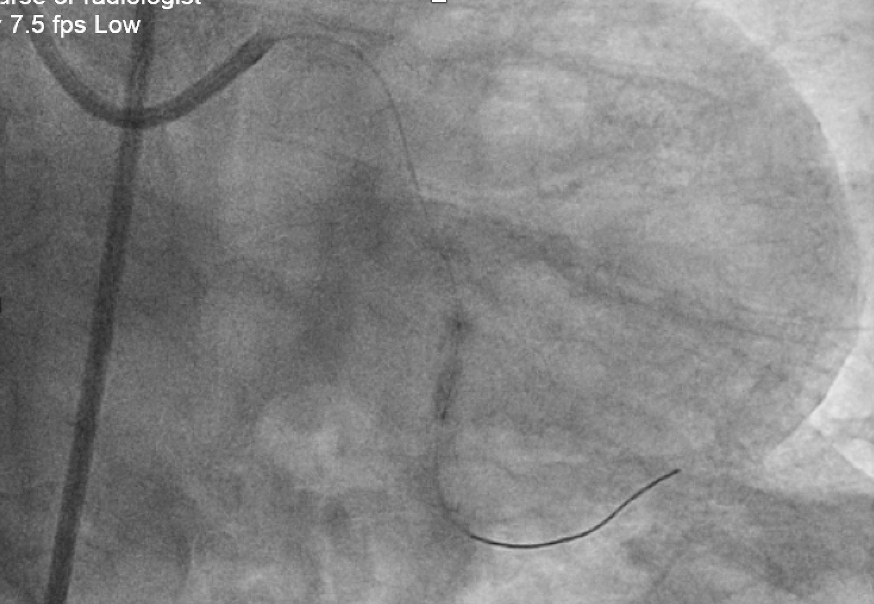

Left femoral access EBU 3.5 7Fr GCSion Blue + microcatheter (Corsair Pro XS) wired to LCx Fail to advance microcatheter

Microcatheter placed as distal as possible, free hand wiring with Rotafloppy wire